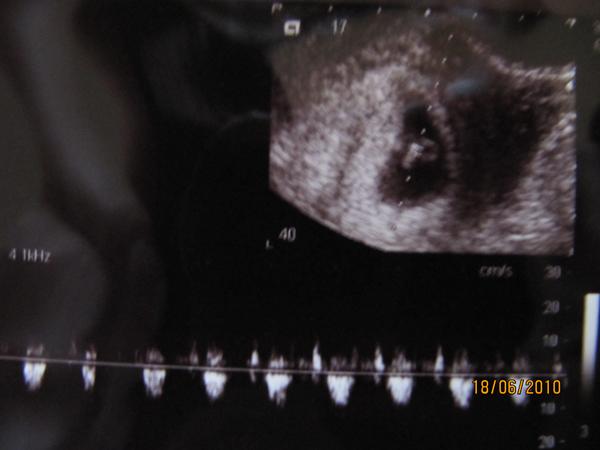

Elbúcsúztunk ma Tapolcáról, meg volt az utolsó ottani UH, ma végre én is láttam, ahogy a babák mindkét kézzel kalimpálva integetnek

olyan megható pillanat volt